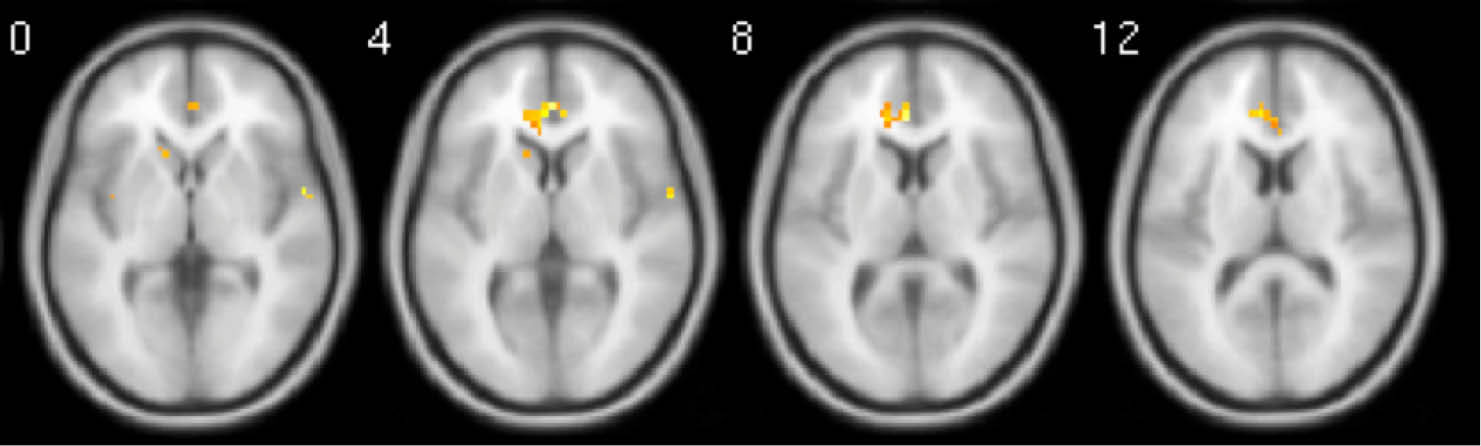

Fig. 3.

Whole brain activation during relaxing moments when contrasted with baseline moments. Activations have been FDR corrected and were only observed in the mPFC. Images are average brain activations across all subjects.

When relaxing moments were compared with baseline moments, a small but significant cluster of activation appeared in the mPFC after FDR correction, but not for the vACC (Fig. 3). Other horizontal slices showed little significant activity. When tingling moments were compared with baseline moments, multiple and significant clusters of activation appeared in the mPFC, insula, and NAcc after FDR correction (Fig. 4).